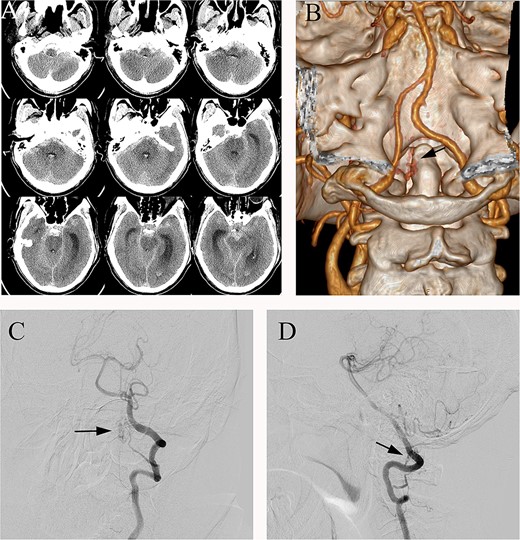

The patient underwent microsurgical treatment of the sDAVF. A minimal midline incision was made between the foramen magnum and C2. Following dissection of the arachnoid membrane, the abnormal dilated venous structure was revealed. Intraoperative indocyanine green (ICG) videoangiography was performed to identify the proximal draining vein, which was filled early with the ICG (Fig. 2A). Then we coagulated the abnormal vein close to the dural (Fig. 2B). Then the arterialized veins were darked in ICG videoangiography (Fig. 2C), preserving the draining veins to avoid spinal cord ischemia. Postoperative DSA confirmed complete obliteration of the fistula, and the patient had an uneventful recovery (Fig. 3).

(A) Intraoperative ICG fluorescence imaging demonstrated that the fistula and abnormal drainage vein (asterisk) developed earlier than the posterior inferior cerebellar artery (PICA). (B) Coagulation of the origin of the abnormal drainage vein. (C) A subsequent ICG imaging confirmed the absence of fistula and drainage vein (asterisk) filling, with previously drainage veins developing later than the vertebral artery and PICA.